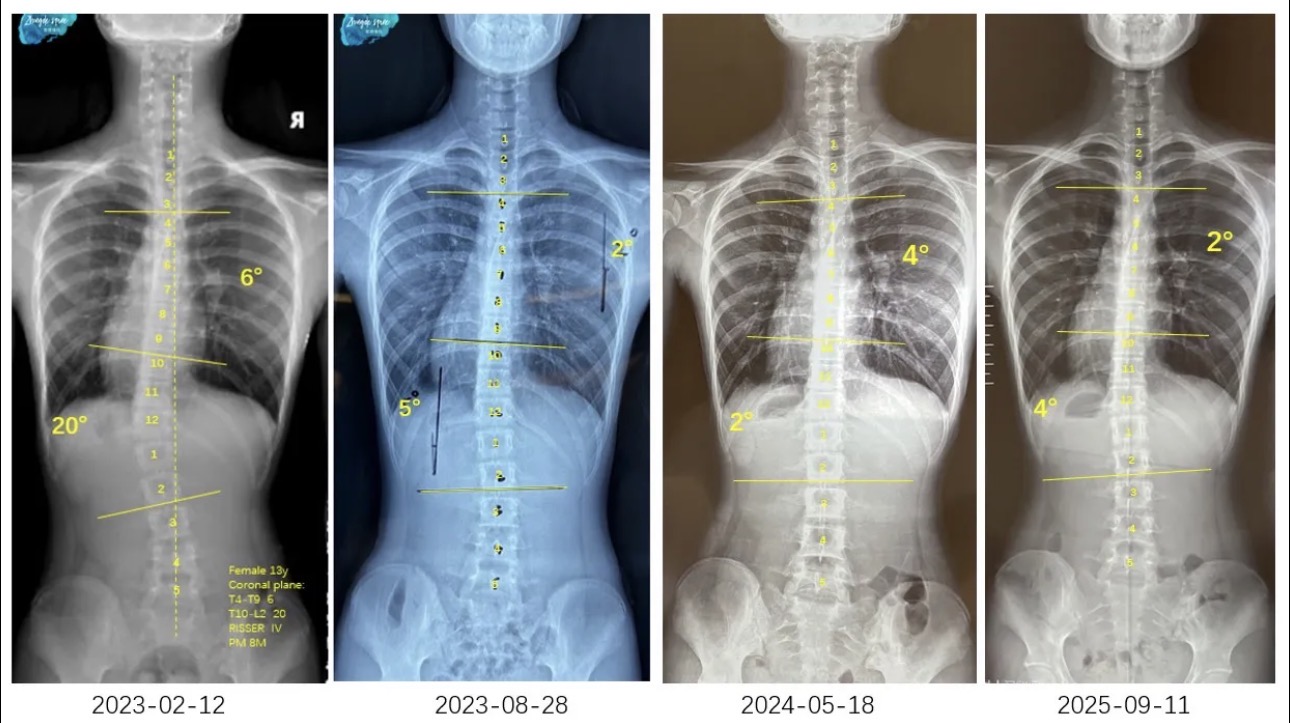

衷德脊柱,我们只关注侧弯保守治疗~

Zhongde Spine, bending no breaking ~